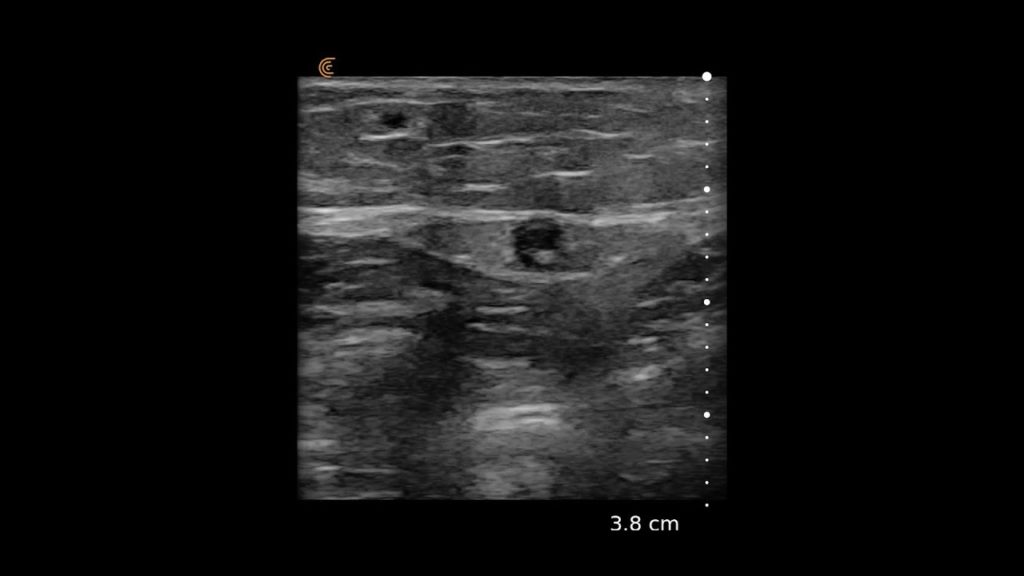

Using the jejunum as an important landmark, the hypoechoic jejunal lymph nodes can be identified. In this video Dr. Edwards explains the ultrasound appearance of normal jejunal nodes.